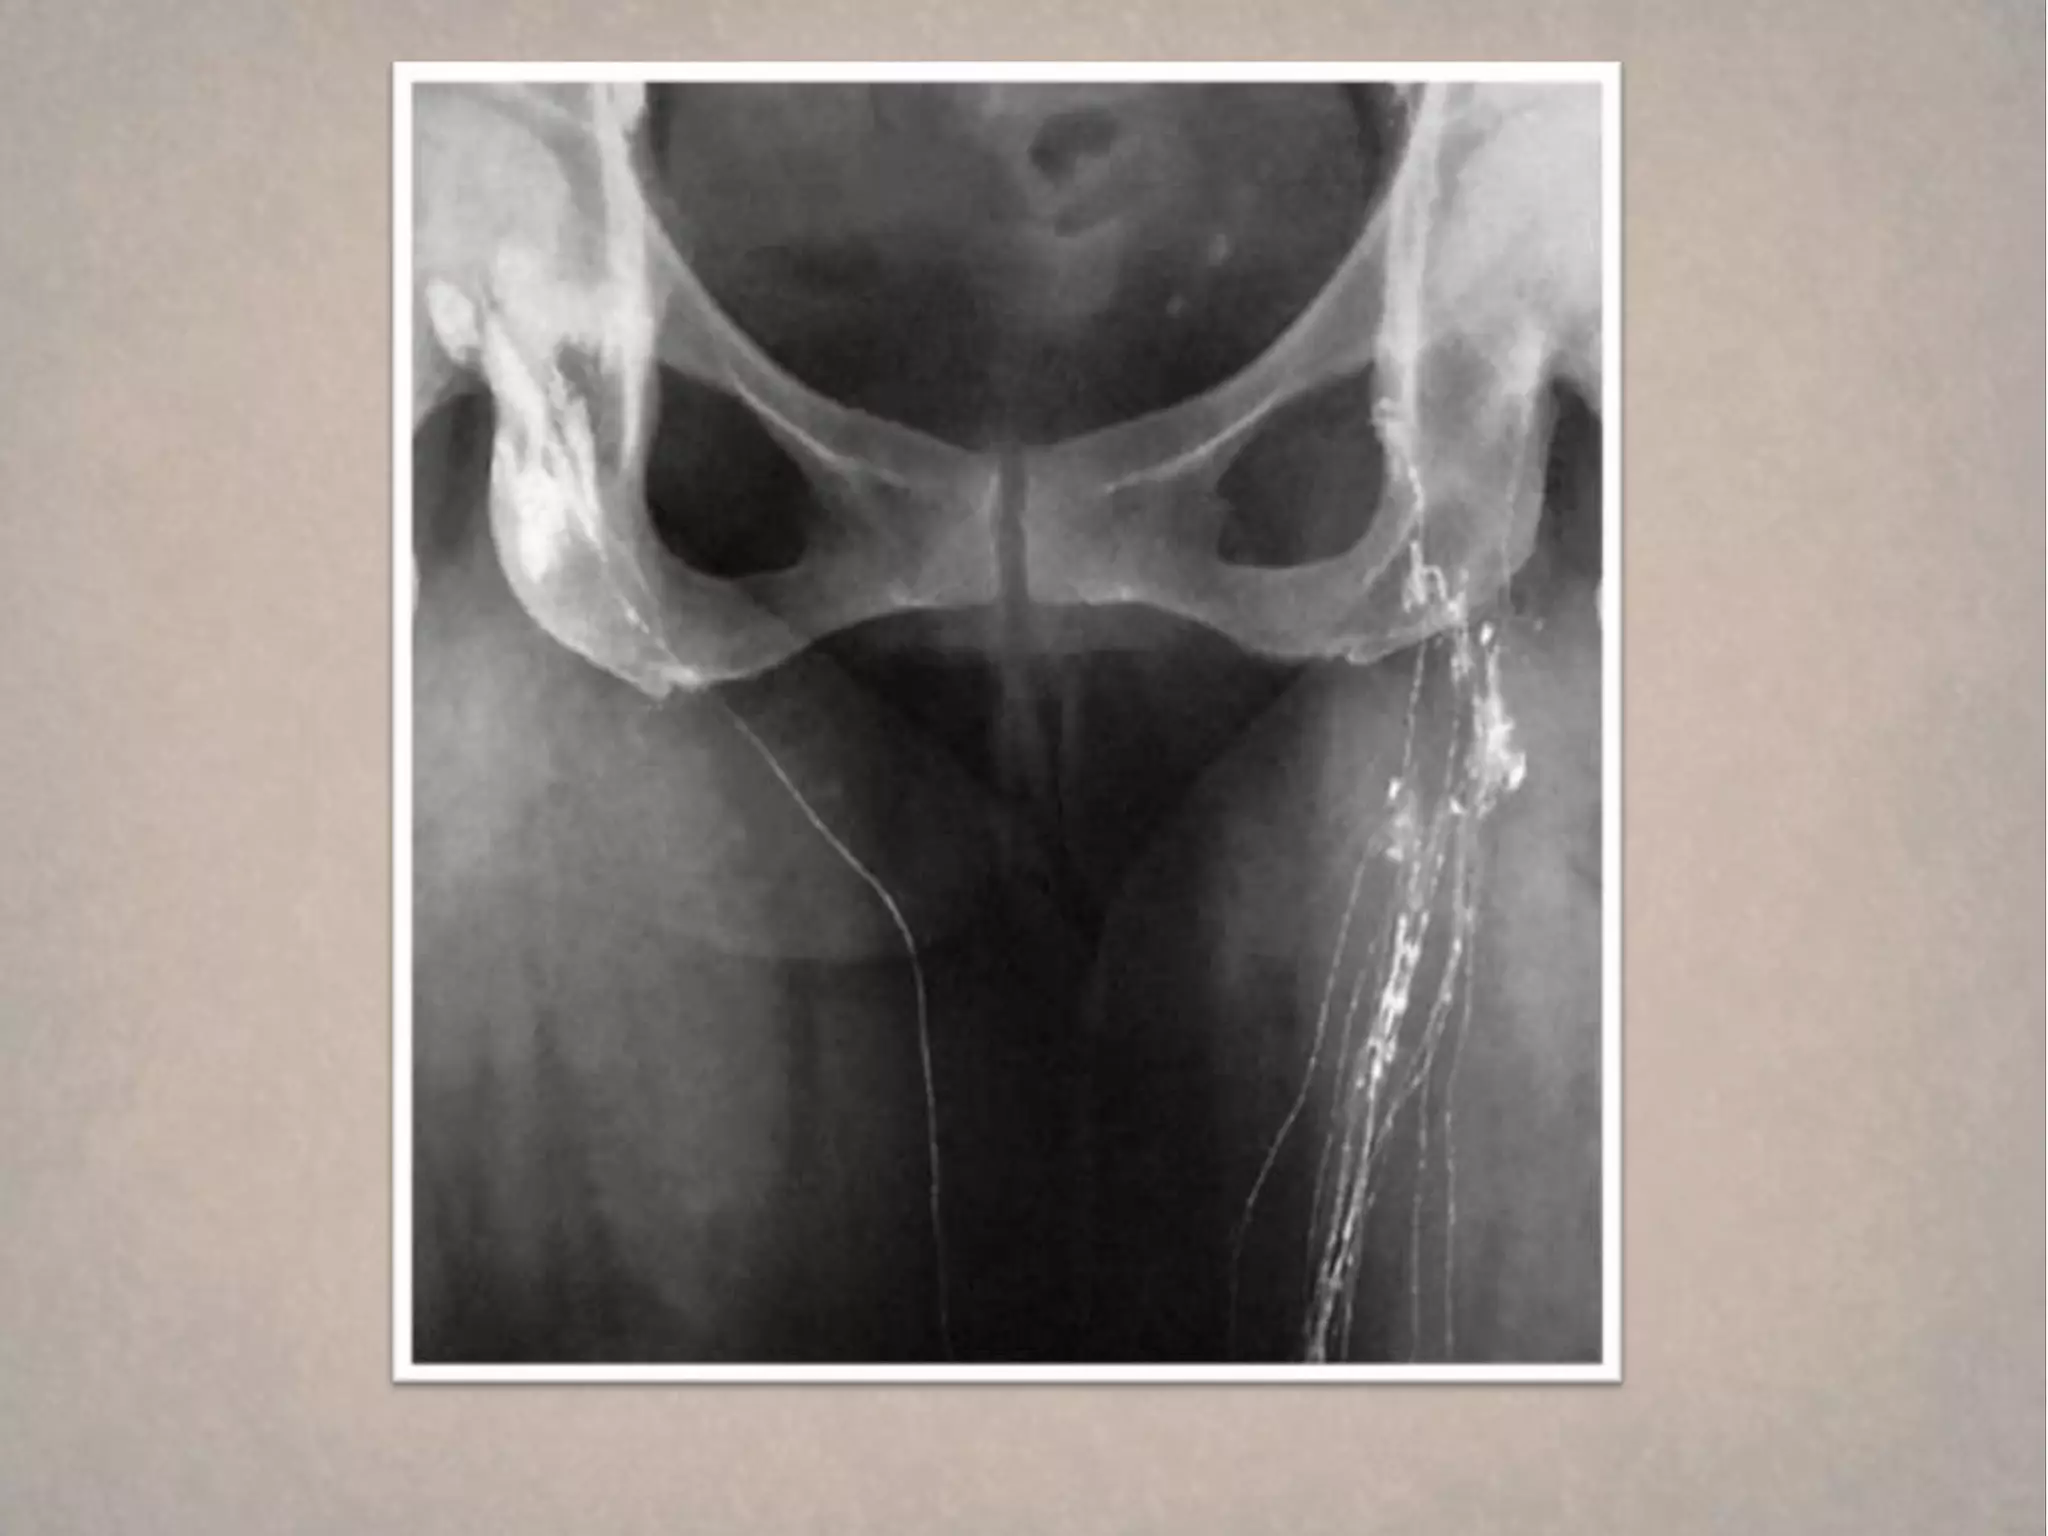

How can we start ?   Figure 1

How can we start ?   Figure 5

How can westart ? Figure 1

How can westart ? Figure 4 DVT

How can westart ? Figure 5